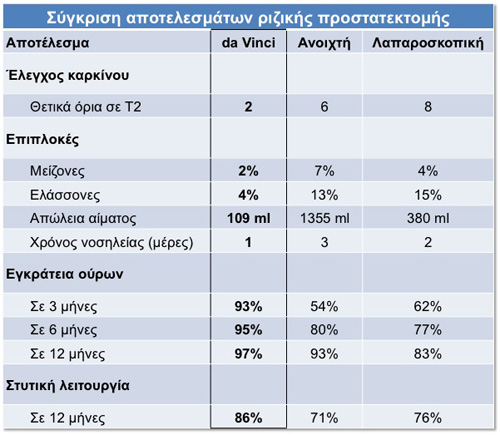

Da Vinci vs. Ανοιχτό Χειρουργείο vs. Λαπαροσκόπιση

Ο παρακάτω πίνακας επικεντρώνεται στα αποτελέσματα μετά από χειρουργείο για καρκίνο του προστάτη (ριζική προστατεκτομή) και συγκρίνει τα καλύτερα αποτελέσματα καθενός από τους τρεις τύπους επέμβασης. Όπως παρατηρείται η da Vinci προστατεκτομή έχει μετρήσιμα αποτελέσματα συγκριτικά με τις άλλες δύο μορφές επέμβασης (την παραδοσιακή ανοιχτή χειρουργική και την συμβατική λαπαροσκοπική ελάχιστα τραυματική επέμβαση)